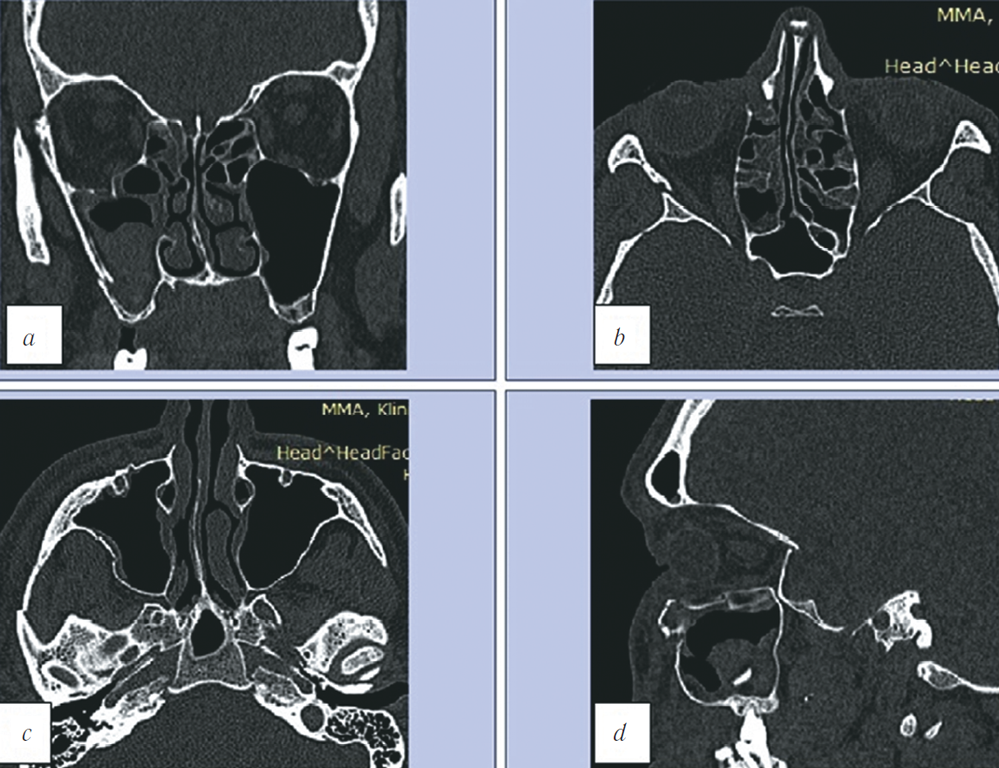

- После измерения объёмов орбит сравнивали результаты до и после реконструктивной операции (рис. 3). При разнице объёмов более 2 мл западение глазного яблока увеличивается на 1 мм и, как следствие, повышается риск развития энофтальма, что является достоверным прогностическим фактором и может быть использовано для оценки эффективности хирургического лечения.

Рис. 3. МСКТ, средняя зона лица, костный режим. 3D-реконструкция (a), аксиальная (b, c) и коронарная (d) реконструкции. Сравнение значений объёмов обеих орбит

Fig. 3. MSCT, midface, bone window. 3D (a), axial (b, c), and coronal (d) reconstructions. Comparison of both orbital volume values